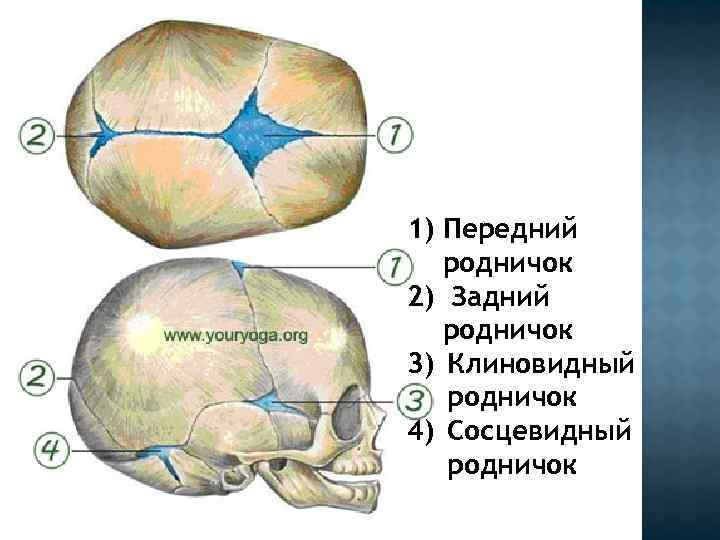

Некоторые краевые участки костей не окостеневают к моменту родов и представлены по-прежнему пластинками соединительной, или перепончатой, ткани. Таковыми оказываются участки в местах соединения нескольких костей, они-то и называются родничками. К моменту рождения у малыша, как правило, имеется шесть родничков — два непарных и два парных.

Роднички, fonticuli cranii. Они представляют собой окостеневшие участки, расположенные в местах образования будущих швов. Известно, что свод черепа на протяжении внутриутробной жизни претерпевает структурные изменения. Первоначально он представлен в форме перепончатого образования, покрывающего сверху головной мозг.

1) Передний родничок, fonticulus anterior , чаще имеет форму ромба, расположен у места схождения швов – сагиттального, венечного и метопического. Родничок сохраняется до 2 лет и к концу второго года окостеневает. 2) Задний родничок, fonticulus posterior , треугольной формы, располагается у места соединения сагиттального шва с ламбдовидным. Окостеневает в начале первого года жизни.

3) Клиновидный родничок, fonticulus sphenoidalis, парный, залегает в переднем отделе боковых поверхностей черепа, между лобной и теменной костями спереди и сверху и большим крылом клиновидной кости и чешуйчатой частью височной кости снизу. Закрывается вскоре после рождения, а иногда даже к концу внутриутробного периода. 4) Сосцевидный родничок, fonticulus mastoideus, также парный, расположен позади предыдущего, у места соединения затылочной чешуи, теменной кости и сосцевидного отростка височной кости. Окостеневает в тот же период, что клиновидный.

1) Передний родничок 2) Задний родничок 3) Клиновидный родничок 4) Сосцевидный родничок